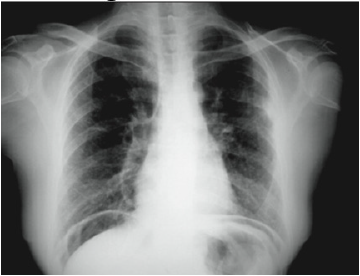

Idoso de 69 anos com quadro de melena há 1 semana e, há 3 horas, referiu surgimento de dor abdominal aguda dufusa mais intensa em epigastro. Estava em uso de diclofenaco diariamente há 1 ano, devido à coxartrose. Nega uso de outras medicações. Foi realizada a seguinte radiografia:

Diante do quadro, assinale a alternativa que apresenta o correto diagnóstico.